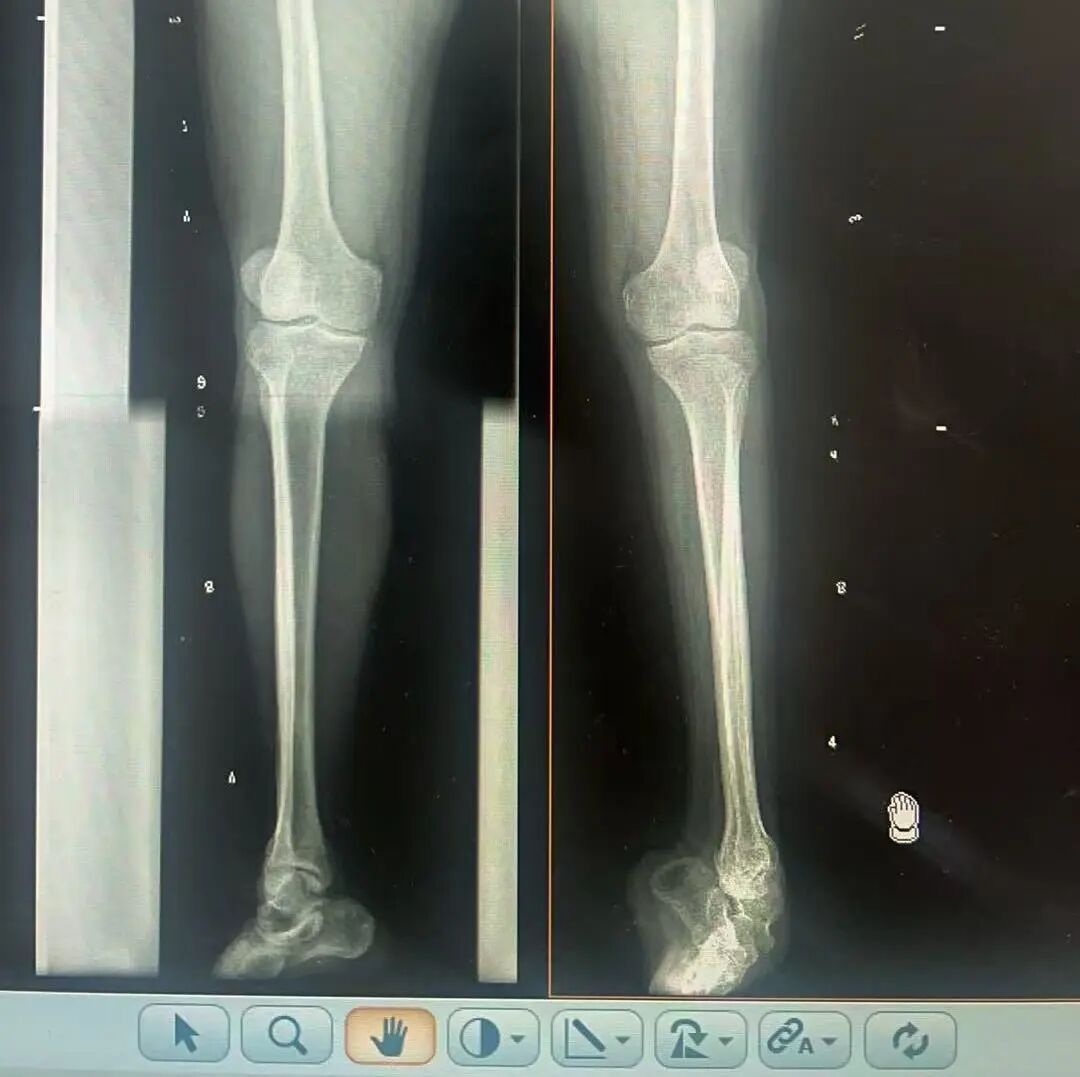

术前X光片 VS 术后治疗效果

骨科随即为阳先生进行了全面的检查。诊断明确而复杂:阳先生患有脊髓灰质炎后遗症、左踝马蹄内翻足、骨盆倾斜……面对这张沉甸甸的诊断书,由肢体功能重建显微修复学科组长郑群龙所带领的医疗团队没有畏惧,“这是一个家庭38年的坚守与期盼,我们必须全力以赴”

针对阳先生的复杂情况,郑群龙医师团队制定了详尽的手术方案:左踝关节融合+马蹄足畸形矫正+跟腱延长+外固定架固定术。手术的核心,正是伊里扎洛夫技术。这项技术如同精密的“时空建筑学”,通过微创安装环形外固定架,前足-后足安装钢环,再将足的钢环与胫骨的固定钢环在踝关节前、后、左、右用带关节的螺纹杆连接,由此构建成一个能体外牵拉调控的三维立体构型,在术后进行精准、缓慢的调整,一寸一寸逐步将畸形的骨骼、软组织恢复到正常位置。

9月1日,在全麻状态下,阳先生接受了伊里扎洛夫外固定架安装术。郑群龙团队在阳先生左足足踝部植入克氏针及半针,安装外固定架,通过支架的机械结构对马蹄内翻畸形进行缓慢、持续的牵拉矫正。术后,郑群龙团队反复指导训练阳先生父子进行外固定架的日常调试,按照预定计划每日调整螺杆,逐渐纠正足部畸形,并配合专业的康复训练,包括踝关节主动及被动活动、下肢肌力训练等项目促进阳先生腿部肢体功能恢复,预防肌肉萎缩及关节僵硬。